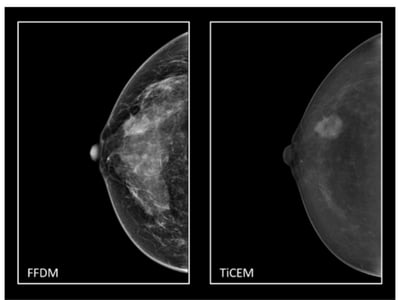

TiCEM- Dedicated Titanium filter optimizes x-ray spectrum for contrast enhanced mammography compared to Copper-filtration

TiCEM – Titanium Contrast-Enhanced Mammography

MAMMOMAT B.brilliant offers you a quick and easy pathway to contrast-enhanced mammography with TiCEM. TiCEM allows for fast identification of potential cancers and rules out inconclusive lesions. Siemens Healthineers is the only vendor with a titanium filter to enable consecutive CEM exams with no interruptions due to tube overheating.

TiCEM (Titanium Contrast Enhanced Mammography)

Challenging cases may require additional diagnostic information for confident decision-making. TiCEM helps to rule out or detect for inconclusive lesions.1